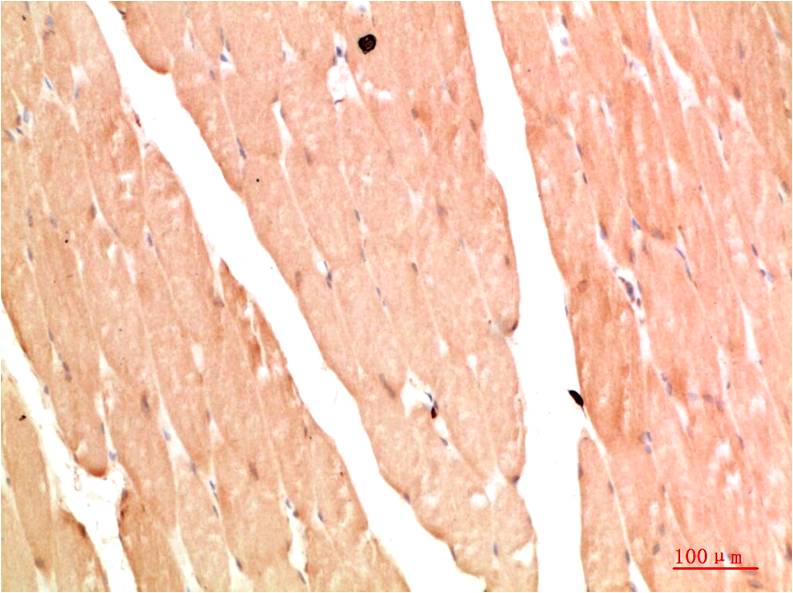

TTR Mouse Monoclonal Antibody(5G9)

Applications :WB, IHC

| Recommended dilutions: | WB 1:1,000-2,000 IHC 1:100-200 |

| Specificity: | The TTR Mouse Monoclonal Antibody can detects endogenous TTR proteins. |